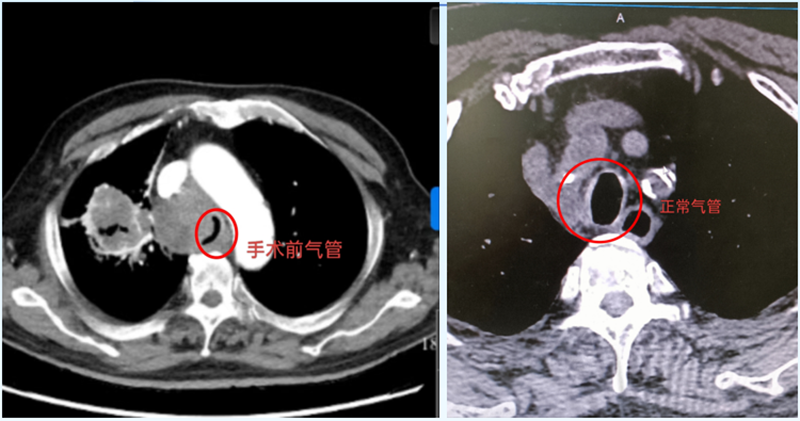

CT影像揭開了兇險:右肺門區(qū)的惡性腫瘤已悄然“逼近”氣道,把氣管擠得只剩一條窄縫?!熬拖裼檬制×瞬弊樱瑲飧疚贿M去!”醫(yī)生快速判斷,立即展開抗炎、平喘治療,暫時為于大爺“松了綁”??烧l也沒想到,這場“呼吸保衛(wèi)戰(zhàn)”才剛剛開始。

次日凌晨,于大爺?shù)暮粑蝗辉俅巍案婕薄?。監(jiān)護儀上的血氧飽和度直線下降,他張著嘴卻發(fā)不出聲音,仿佛有只無形的手死死扼住喉嚨。呼吸內(nèi)鏡中心主任劉傳偉聞訊趕來,盯著影像片眉頭緊鎖:“腫瘤壓迫氣管成了‘細線’,必須立刻撐開氣道,否有生命危險!

支氣管鏡鏡頭下,氣道中下段被瘤體壓得只剩發(fā)絲寬,粘痰像“絆腳石”堵在狹窄處。劉傳偉主任穩(wěn)住鏡身,助手精準(zhǔn)遞過支架推送器——“3、2、1,釋放!”隨著“咔嗒”一聲輕響,支架如“微型橋梁”撐開塌陷的氣管。

“呼——”于大爺突然長舒一口氣,監(jiān)護儀上的血氧值“蹭”地回升到98%!他眨了眨眼,虛弱卻清晰地說:“活過來了……謝謝你們……”這口“救命氣”,不僅讓病房里的家屬紅了眼眶,更讓多科室協(xié)作的“生命防線”終于筑牢。

如今,于大爺已能正常吃飯、散步,后續(xù)抗腫瘤治療正在穩(wěn)步推進。這枚11厘米長的L型支架,不僅是醫(yī)生用專業(yè)與速度編織的“呼吸通道”,更藏著醫(yī)者對生命的敬畏:“哪怕只有1%的希望,我們也要拼盡全力?!?/span>